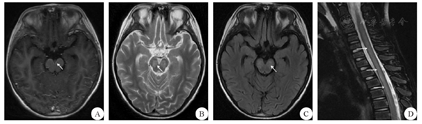

患儿 男,9岁,因"发热头痛5 d"于2019年3月8日入院。患儿母亲代诉患儿于入院前5 d无明显诱因出现发热、头痛,热型不规则,体温最高达38.9 ℃,头痛呈阵发性前额部疼痛,发热时明显,热退后疼痛稍缓解。于当地医院诊治后仍有反复发热,遂转至我院进一步治疗。患儿既往体质一般,否认特殊病史,个人史和家族史均无特殊,否认蚊虫叮咬、动物抓咬伤和传染性疾病接触史,生长发育状况与正常同龄儿童相仿。内科体检:体温36.4 ℃,脉搏95次/min,呼吸频率22次/min,血压95/58 mmHg(1 mmHg=0.133 kPa),咽红,咽峡部未见明显疱疹,双侧扁桃体Ⅱ度肿大,心肺腹无异常,手足无皮疹,双下肢无水肿。神经系统体检:神志清楚,精神反应稍差,体检欠配合,双侧瞳孔等大等圆,对光反射灵敏,颅神经征(-);四肢肌力、肌张力及浅感觉均正常,四肢反射对称,腱反射(++),颈抗阳性,双侧Kernig征、Brudzinski征阴性,病理征未引出。辅助检查:血常规示单核细胞比例增高(14.6%,正常值3.0%~10.0%)。电解质示钾离子减低(3.05 mmol/L,正常值3.50~5.30 mmol/L)、钠离子减低(132.1 mmol/L,正常值135.0~145.0 mmol/L)。大小便常规、肝肾功能、心肌酶、C反应蛋白、血沉、术前抗体三项均大致正常,呼吸道病毒七联检均阴性。腰椎穿刺脑脊液常规检查示其外观无色、透明,压力未测,白细胞计数增高[220×106/L,正常值(0~10)×106/L],单个核细胞比例增高达99%;脑脊液细胞学检查示白细胞计数高度增高(213.0×106/L),以淋巴细胞为主;脑脊液生化示蛋白水平升高(1562 mg/L,正常值150~450 mg/L),其余糖、氯化物水平均正常。颅脑及脊髓MRI增强扫描示双侧大脑半球及脑干表面柔脑膜稍增厚强化,C2~T11椎体水平脊髓内异常信号,增强后可见强化,部分脊膜及双侧脊神经强化,并可见脑干异常信号(图1)。对患儿予以抗感染、脱水等对症支持处理,1周后患儿逐渐出现胡言乱语、意识障碍及大小便障碍,双上肢肌力下降至4级,右下肢肌力下降至3级,左下肢肌力下降至2级。复查腰穿脑脊液结果较上次变化不大,脑脊液及血清抗水通道蛋白4(AQP4)、髓鞘碱性蛋白(MBP)、髓鞘少突胶质细胞糖蛋白(MOG)抗体阴性;脑脊液及血清N-甲基-D-天冬氨酸受体(NMDAR)型抗体、α-氨基-3-羟基-5-甲基-4-异恶唑丙酸(AMPA)1型抗体、AMPA2型抗体、抗富亮氨酸胶质瘤失活蛋白抗体、抗接触蛋白关联蛋白2(CASPR2)、抗γ-氨基丁酸B型(GABAB)受体抗体IgG阴性;脑脊液病原微生物高通量基因检测发现EBV,诊断为EBV感染性脑膜脑脊髓炎。对患儿予以加用阿昔洛韦抗病毒、大剂量甲强龙冲击治疗以及脱水、维持水电解质平衡等对症支持处理,患儿症状高峰期持续4 d后病情逐渐好转,1个月后基本恢复正常,仅遗留双下肢肌力稍差(4级)。9个月后复查患儿头颅及脊髓MRI,示恢复至正常(图2)。

A:增强扫描示脑干表面柔脑膜稍增厚强化;B:T2WI示脑干弥漫性高信号;C:液体衰减反转恢复序列示脑干弥漫性高信号;D:T2WI示长节段脊髓病变;箭头所示为病变